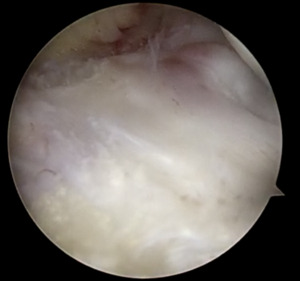

The tear pattern involved the periphery of the lateral meniscus, extending along the meniscocapsular junction from zones I though III (Figure 6).

The anterior and posterior roots of the lateral meniscus were intact (Figure 7).